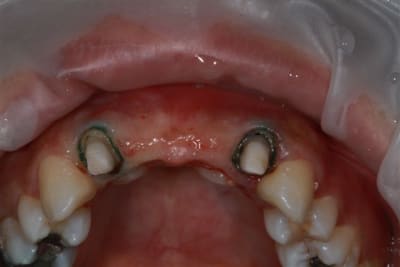

Patiente sympa, 30 ans, un bridge ceramo-métal fait il y a 10 ans, en fin de vie.

En réalité je sais déjà ce que je vais faire, mais implants, bridge ou pourquoi pas adjointe???